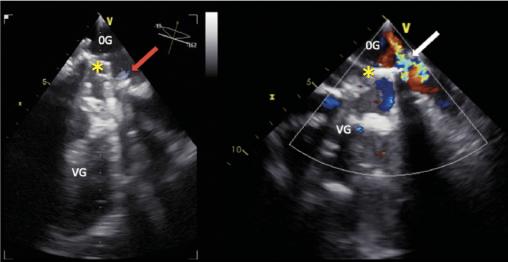

Cette femme de 67 ans avait une asthénie et par intermittence des urines sombres. Une insuffisance mitrale rhumatismale avait été traitée 22 ans auparavant par remplacement valvulaire chirurgical. Le bilan biologique révélait une anémie (7,6 g/dL) normochrome normocytaire régénérative (taux de réticulocytes à 278 000/mm3), un taux de lacticodéshydrogénase à 2 688 UI/L, un taux d’haptoglobine inférieur au seuil de détection et un taux normal de bilirubine totale. Le frottis sanguin (fig. 1 ) notait de très nombreux schizocytes (plus de 500/1 000). L’échocardiographie transœsophagienne (ETO)montrait la présence d’une végétation et une fuite prothétique (fig. 2 ). Il s’agissait d’une endocardite infectieuse à Pseudomonas aeruginosa compliquée d’une désinsertion de valve prothétique.